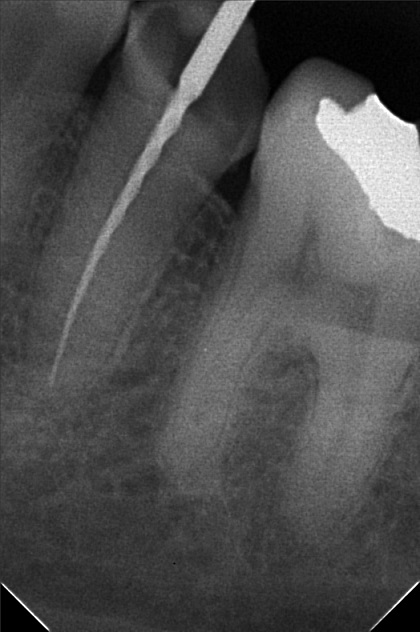

- 9/24/22 - Check up & Xray 10/01/22 - RCT 18mm , formacresol #35 10/08/22- RCT 17mm, campenol 10/15/22- 17.5MM PULP DEVITALIZER PAD done 11/05/22- Zirconia/LC 16 11/19/22- OP/Install Of Crowns